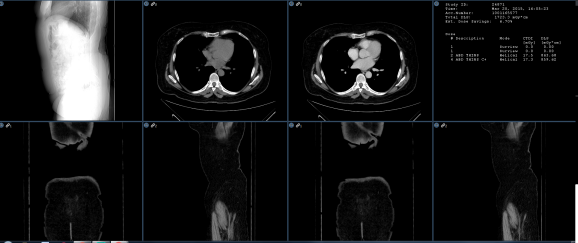

All Study

When this option is selected along with the Grids matrix layout, the viewer will load all open studies (current and prior) into available image frames. If there are too many images for the number of frames available, a virtual monitor will appear in the top right corner of the image frame in order to accommodate the images. These are shown highlighted in yellow in the image below. The selected virtual monitor is highlighted red.

Note: A macro shortcut can be created to enable switching back and forth between the virtual monitors.